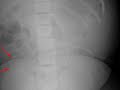

This is a patient who is status post renal transplantation. In the left lower quadrant of the abdomen, there is a percutaneous nephrostomy tube as well as a nephroureteral stent within a left lower quadrant transplant kidney. In the right lower quadrant as indicated by the red arrows, there is a calcified mass with a reniform shape. This is the patients previous right lower quadrant transplant kidney which has failed. The reason why we can visualize the right sided transplant kidney so well as opposed to the left transplant kidney is because of the extensive calcification. The distribution of the calcification is diffuse but predominantly involves the cortex of the transplant kidney as opposed to the medulla. The findings are most consistent with chronic transplant rejection, which is the diagnosis in this case. The other most common cause of cortical nephocalcinosis is chronic glomerulonephritis.